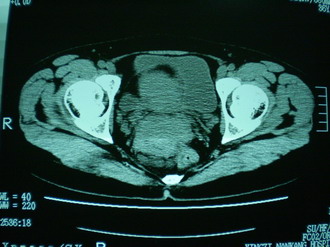

子宫增大,内可见类三角形低密度区,子宫后方可见类圆形团块状影,内部密度不均匀,可见靶样结构,结合病史考虑1子宫后方宫外孕(宫内假孕囊形成)2子宫肌瘤合并妊娠

子宫明显前倾,增大,宫颈增大呈分叶状。子宫直肠窝见不规则形水样低密度。(膀胱胀尿不理想)

考虑:1、宫颈部占位;

2、子宫直肠窝少量积液(盆腔炎所致)。

考虑肌瘤堵塞子宫颈管导致宫腔积液。

1、前曲子宫,2、宫颈部占位?3、盆腔及右输卵管积液?宫内积血?4、左侧卵巢囊肿。